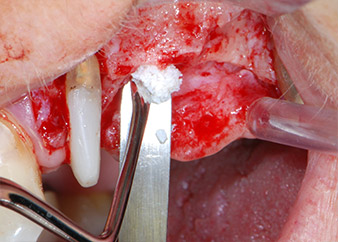

Vor der Insertion der Implantate wurde infiziertes Weichgewebe im Implantationsbereich und um das Abutment mit einem Instrument entfernt, das laut Hersteller primär zur Knochenbearbeitung und zum Sammeln von Knochenspänen vorgesehen ist (Piezomed, Einsatz B5) (Abb. 6 und 7).

Im folgenden Schritt wurde das jeweilige Implantatbett an den Positionen 25 und 26 mit rotierenden Instrumenten in einem Winkelstück mit einem Übersetzungsverhältnis von 20:1 (WS-75 L G, W&H) und einem vor Kurzem aktualisierten leistungsstarken Implantatmotor präpariert (Implantmed, W&H) (Abb. 8 und 19).